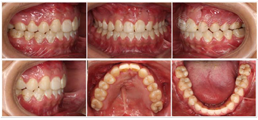

4.术前调整(图7):25纳入牙弓,去除牵张器,继续排齐整平牙列,匹配牙弓,去除咬合干扰;患者口腔卫生差,给予牙周洁治,加强口腔宣教。

5.双颌手术建立终末咬合,术后精细调整(图8)。

6.完成(图9,图10):患者因异地无法继续复诊,与其协商后结束治疗。主动矫治共36个月,术后给予患者采用压膜保持器(12个月),后换用Hawley保持器至今。嘱患者继续进行牙体治疗及鼻唇整复术。